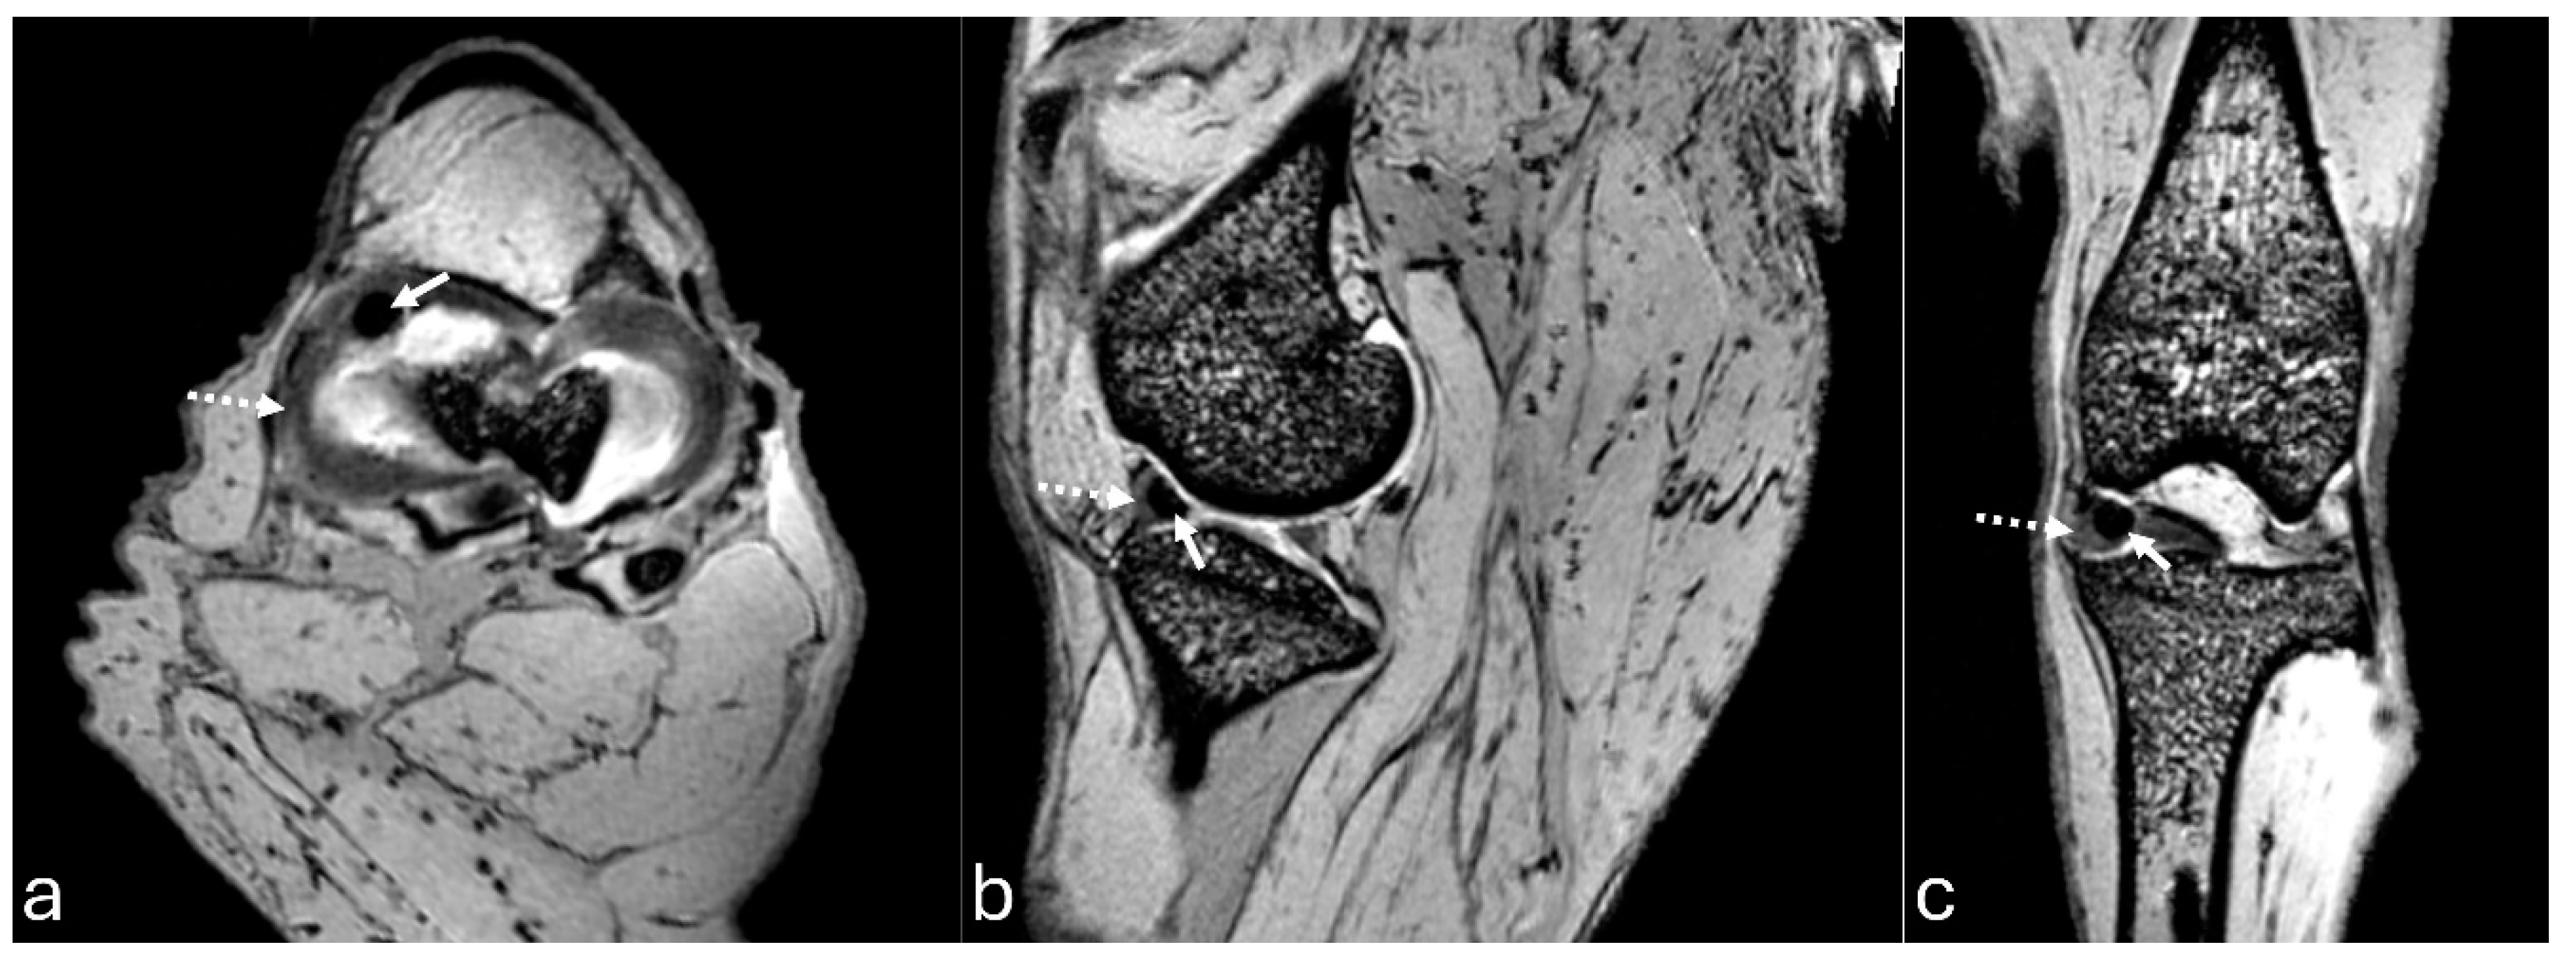

Figure 7. 3D-DESS imaging at 7-T MRI on transversal (a), sagittal (b), and dorsal (c) planes of an adult puma stifle joint (Puma concolor). Observe the medial meniscus (dashed arrow) and the mineralization of the cranial horn of the medial meniscus (arrow).

The MRI images allowed for more precise visualization of the cranial and caudal cruciate ligaments (Figure 6), the C-type shape of both menisci on the transverse plane, and the triangular appearance on the sagittal plane, with the medial meniscus being larger than the lateral one (Figure 7 and Figure 8). Mineralization was easily identified in the cranial horn of the medial meniscus as a rounded structure with a hypointense signal (3D-DESS sequence). High-resolution imaging of subchondral bone and cartilage was also visualized (Figure 9).

The role of meniscal mineralization is always controversial in domestic and wild felines [10,21,22,23,24]. In wild felines, medial meniscal mineralization has been described in Puma concolor, Panthera tigris, Acinonyx jubatus, Panthera leo, Panthera tigris, Panthera pardus, and Leopardus tigrinus, but it was not associated with joint degenerative processes [10,11,21,23,25], as verified in the present study in the imaging analysis. Conversely, in domestic felines, one study attributed the presence of mineralization to degenerative joint disease [22], and another found that cats with a ruptured cranial cruciate ligament had a higher percentage of medium and large mineralizations compared to those without rupture [24].

In the present study, meniscal mineralization was detected in three adults and one young animal. The young animal had meniscal mineralization of a smaller size and a lower HU value than the adults. A study involving large felines suggested that meniscal ossicles mineralize with skeletal maturation and become radiographically visible around one year of age or in the last half of skeletal maturation [10]. The absence of meniscal mineralization in a young animal could be justified by this statement, but there were three adults in which mineralization was not identified, indicating that meniscal mineralization is not a constant finding. Furthermore, a study reported that Panthera leo, Panthera tigris, and Panthera leo with meniscal ossicles typically had a lateral fabella but often lacked the medial fabella of the gastrocnemius muscle [10]. This contrasts with the present study, where all animals had all sesamoids regardless of the presence or absence of mineralized medial meniscus.